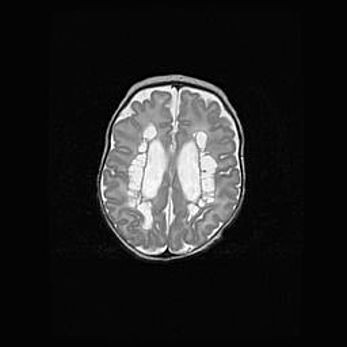

Сообщающаяся гидроцефалия. Кистозная энцефаломаляция головного мозга.

Возраст: 3 месяца 4 дня

Вес: 3100 г

Пол: женский

Окружность головы: 34 см

Срок гестации: 31 неделя

Кистозная энцефаломаляция головного мозга - одна из форм поражения головного мозга в детском возрасте. Характеризуется возникновением множественных и распространённых кист в коре, белом веществе и подкорковых образованиях головного мозга у плодов, новорождённых и детей раннего возраста. Развитие кистозной энцефаломаляции связано с внутриутробной асфиксией и гипотонией, родовой травмой, тромбозом синусов, пороками развития сосудов, инфекциями, сепсисом и другими причинами. Наиболее значимые инфекционные агенты: вирусы простого герпеса, цитомегалии, краснухи, токсоплазмы, энтеробактерии, золотистый стафилококк и другие.